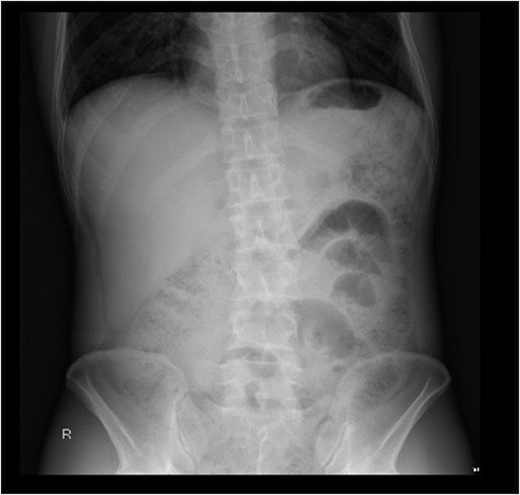

Following imaging and discussion with the patient, we proceeded to emergency laparotomy. On evaluating the small bowel, an enterotomy was noted in the mid jejunum due to a protruding fractured piece of frog bone (see Figs 3 and 4). There was associated localised peritonitis, but no gross peritoneal contamination. A sample was taken for culture and sensitivity, but no growth was ultimately seen. A decision was made to proceed with a primary repair of the enterotomy as the surrounding small bowel tissue was healthy, and this was performed in two-layers with interrupted 4–0 PDS. An extensive abdominal washout was performed prior to closure. The patient made an uneventful post-operative recovery and was discharged home well on post-operative Day 7.